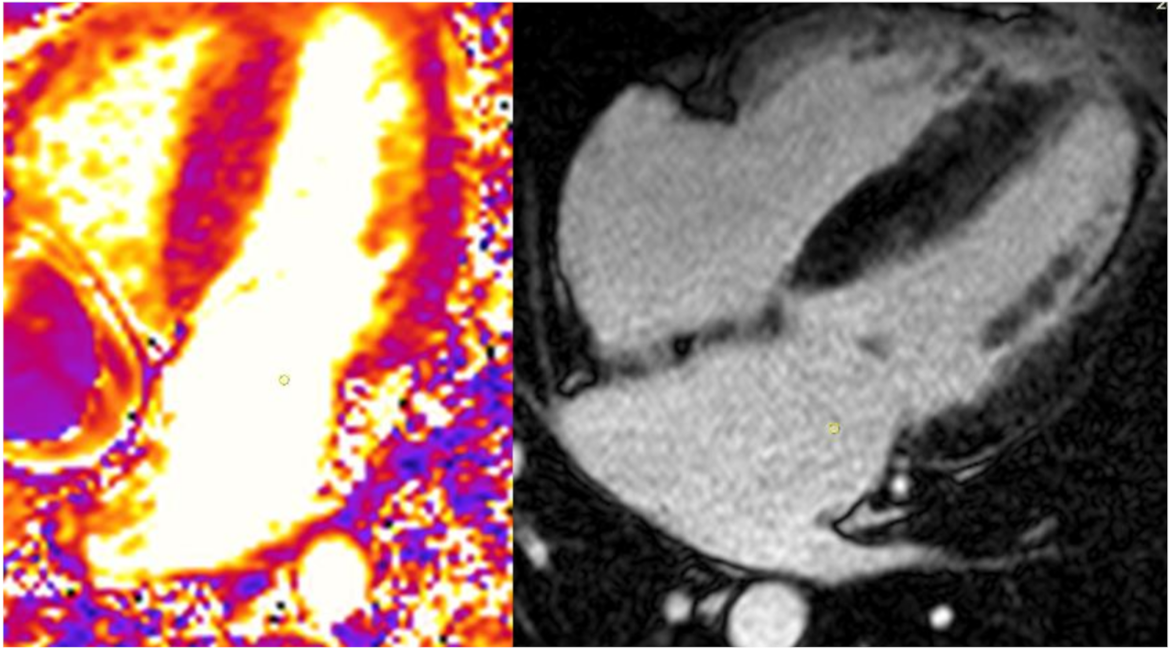

3.2. Cardiac MRI

- T1 lowering is a sensitive sign of FD cardiomyopathy that precedes LVH and late gadolinium enhancement but is not yet an accepted trigger for therapy;

- Late gadolinium enhancement is an accepted trigger for initiation of therapy but there remain questions regarding efficacy once identified.